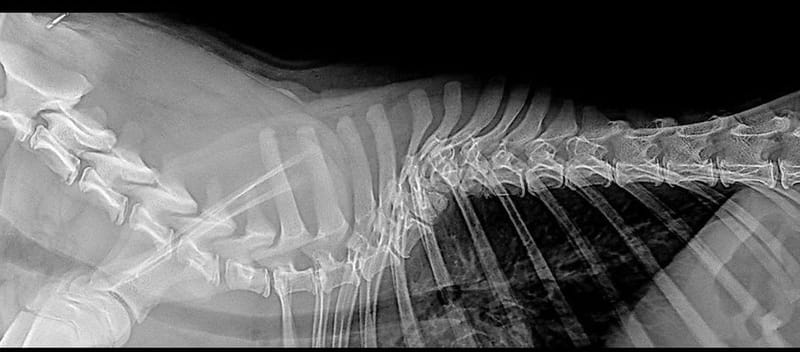

Le dos

Les myélopathies et les hernies chez le bouledogue